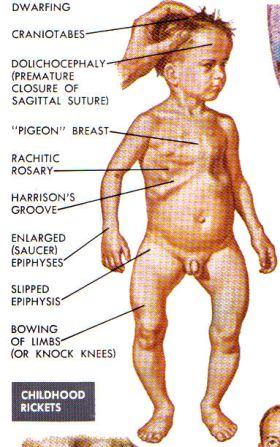

Rahitism este o tulburare a metabolismului osos întâlnită în perioada copilăriei, caracterizată prin mineralizare insuficientă a oaselor în timpul creșterii. În general este legată de dezechilibre ale nutrienților utilizați în formarea scheletului, iar în funcție de cauză poate contribui la o dezvoltare anormală a oaselor și a dinților.

Semnele pot include deformări osoase, încetinirea ritmului de creștere, sensibilitate sau durere osoasă și întârzieri de dezvoltare dentară, însă manifestările variază. Factorii care pot crește riscul includ alimentația inadecvată și expunerea insuficientă la lumina naturală; evaluarea și managementul adecvat trebuie discutate cu un medic pediatru sau un specialist, care poate recomanda investigații și măsuri individualizate. Este important ca orice suspiciune să fie evaluată clinic, deoarece intervențiile optime depind de cauzele specifice.

La sugari și copiii mici, manifestările asociate rahitismului pot fi variate și adesea subtile; ele pot include semne precum:

Dacă observați oricare dintre aceste semne, este important să discutați cu medicul pediatru pentru evaluare și investigații adecvate; specialiștii pot recomanda analize și monitorizare pentru a clarifica cauzele. Măsuri generale, precum o alimentație echilibrată și o expunere moderată la soare, pot contribui la sănătatea oaselor, dar orice intervenție specifică ar trebui stabilită împreună cu un profesionist. Atenție: pentru informații suplimentare despre rahitism, puteți consulta resursele disponibile aici.

Dacă observați la copil semne sugestive de tulburare a metabolismului osos, este indicat să solicitați evaluarea unui medic pediatru. Manifestări precum întârzieri în creștere, dureri sau deformări ale oaselor, hipotonie musculară sau probleme în erupția dinților pot semnala necesitatea unor investigații. Consultul prompt poate ajuta la identificarea cauzelor și la stabilirea măsurilor adecvate fără a emite un diagnostic personal în absența examinării clinice.

R: Semnele pot include întârzierea mersului, dureri sau slăbiciune musculară, deformări ale toracelui sau picioarelor, întârzieri în creştere şi probleme dentare; dacă observaţi astfel de modificări, este importantă evaluarea medicală.